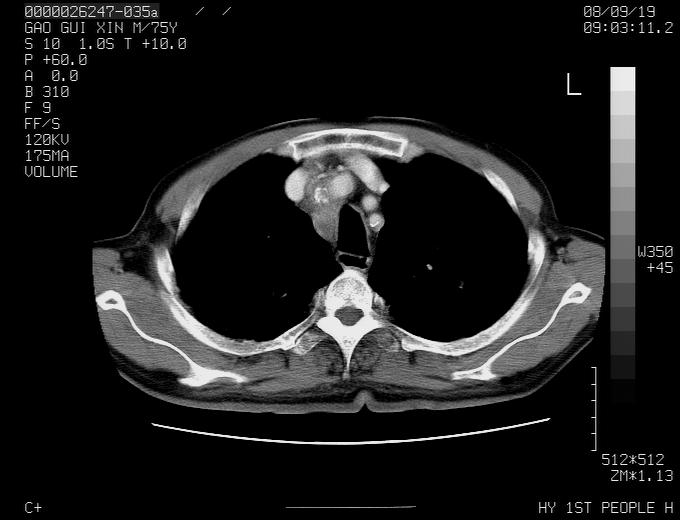

感谢各位老师的意见,左上肺病灶,我本人趋向结核,原因:左上肺见两个类圆形结节,仔细回顾4月份ct似乎原片在该处有条片状密度增高影,强化不明显。

现上传增强片,请各位老师仔细帮我看一下。

右上肺可见条索状影,并可见钙化,左上肺结节可以考虑为结核球,但气管前腔静脉后有肿大淋巴结,本人觉得左上肺结节不能排除转移瘤的可能,右上肺为陈旧性结核灶。

左肺上叶周围性肺癌并纵隔多组lnm.不可能是tb.

左肺上叶尖段瘢痕癌并纵隔淋巴结转移解释更好一些.

左肺周围癌并纵隔淋巴结转移,另一小结节是血管影

1)左肺上叶尖段周围型肺癌并纵隔淋巴结转移。2)冠状动脉及主动脉钙化。